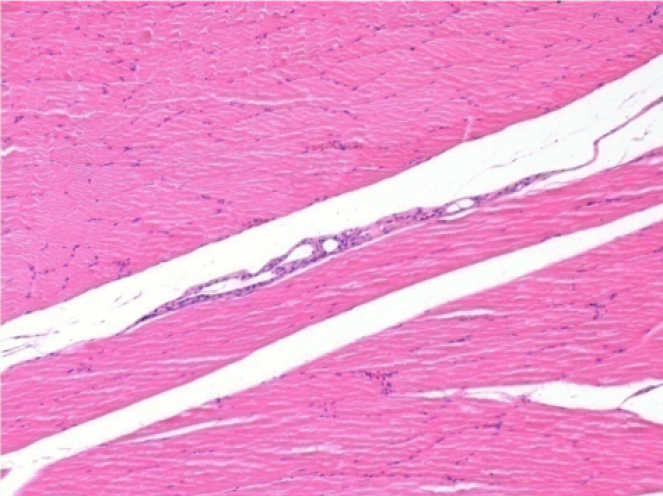

3 months (D90)after Endopeel Injection 0.1ml in the right pretibial muscle.

What is seen in black on the pictures is not a necrosis like could imagine some scientifics !

In fact, 4 conclusions have to be taken in consideration